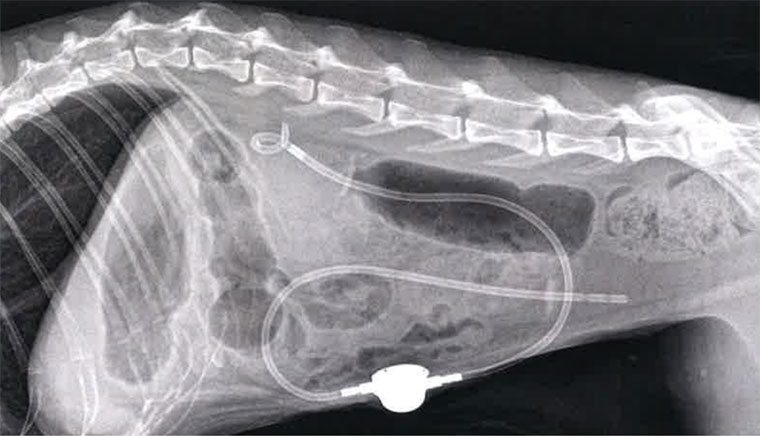

3.SUBシステム (Subcutaneous Ureteral Bypass)

近年、猫の尿管結石の治療において、特に従来の外科手術では対応が難しかった症例や、より長期的な尿流の確保が必要な症例で、このSUBシステム(皮下尿管バイパスシステム)が画期的な治療選択肢として注目されています。

これは、閉塞した尿管を迂回し、腎臓から膀胱へ直接尿を流す人工的な通路を体内に作成するものです。

SUBシステムってどんな仕組み?:

SUBシステムは、猫の尿管閉塞に対して開発された、腎臓と膀胱をつなぐ特別なチューブです。以下の3つの主要な部品で構成されています。

- 腎臓側カテーテル:

腎臓の中にある「腎盂(じんう)」という尿を集める部分に挿入され、腎臓で作られた尿を効率よく吸い出すチューブです。 - 胱側カテーテル:

膀胱の中に挿入され、腎臓側カテーテルから流れてくる尿を受け入れ、おしっことして体外へ排出する準備をします。 - 皮下ポート:

これら2つのカテーテルを体の皮膚の下(通常、肋骨の下あたり)でつなぐ「つなぎ目」のような装置です。このポートは、外から特殊な針を刺すことで、尿を採取したり、チューブが詰まりそうになったときに洗浄(フラッシング)したりするために使えます。これにより、体に負担をかけずにシステムのメンテナンスが可能です。

レントゲンでどう見える?:

SUBシステムが体内にきちんと設置されると、レントゲン画像では特徴的な形で見えます。

腎臓から膀胱へ向かって、ゆるやかに曲がった細いチューブがはっきりと写り、腹壁の皮膚の下には、白くて丸い皮下ポートが確認できます。

これにより、システムが正しく機能しているかを確認できます。

SUBシステムのメンテナンス

SUBシステムを設置した場合は、皮下ポートからの定期的な洗浄(生理食塩水でのフラッシング)が必要になることがあります。これにより、チューブの閉塞を防ぎ、システムの機能を長く保ちます。